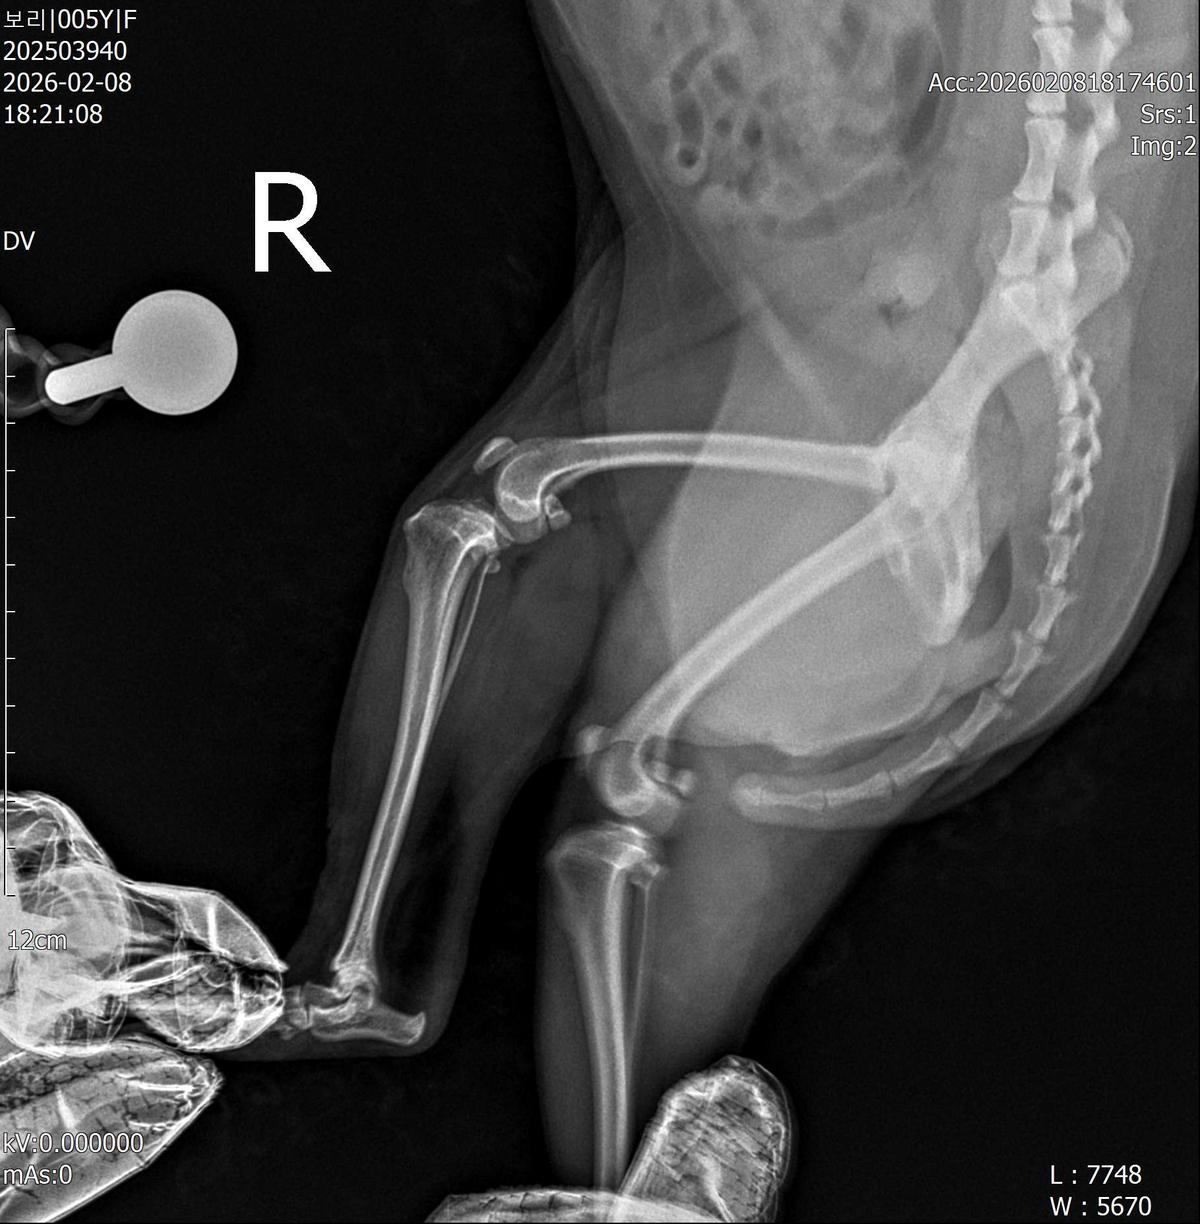

강아지 슬개골탈구 진단 받았습니다 몇군데 병원을 다녀봤는데 진단이 달라 궁금해서 질문 해봅니다 일단 저희 강아지는 오른쪽 다리를 갑자기 들고 다니고 절어 병원을 방문하게 되었고요 왼쪽은 증상이 없지만 오른쪽만 있는 상태였습니다 첫번째랑 두번째 병원에서는 슬개골 탈구 진행중이고 왼쪽이 3기 오른쪽이 2기 정도라고 했습니다 하지만 왼쪽은 아예 빠져있어 증상도 없고 아파하지도 않는다고 했고 오른쪽은 빠졌다 안빠졌다 해서 증상이 있다고 했고 십자인대가 파열된 걸론 보이지 않는다고 했습니다 그래서 양쪽 슬개골탈구 수술만 진행하면 된다고 했고요 근데 세번째 병원에서는 둘다 왼쪽이 좀 더 심한 슬개골 탈구 3기 정도라고 했고 오른쪽만 십자인대 부분파열이 보인다고 했습니다 그래서 십자인대 파열이 아닌 왼쪽은 굳이 수술할 필요가 없고 나중에 십자인대 파열이 오거나 증상이 나타나면 그때 수술하면 된다고 했습니다 그래서 오른쪽 슬개골탈구 수술과 tplo를 하는 방식으로 수술을 한다고 했습니다 여기서 궁금한점은 1. 십자인대 파열이 사진상으론 보이지 않는다고 하는데 사진상으로 알 수 있는 건가요? 2. 십자인대 파열이 아니면 슬개골탈구 수술을 굳이 할 필요 없다고 하셨는데 맞는 건가요? 3. 꼭 슬개골탈구와 십자인대 수술을 같이 해야 결과과 더 좋아지나요? 4. 사진상으로 십자인대와 슬개골 수술을 같이 해야할까요? 5. tplo 수술방법이 가장 안전하고 좋은 수술방법인가요? 6. 슬개골탈구로 인해 십자인대가 끊어지는건 아니라고 들었는데 맞나요? 슬개골 탈구 수술로 십자인대를 예방할 수 있나요?